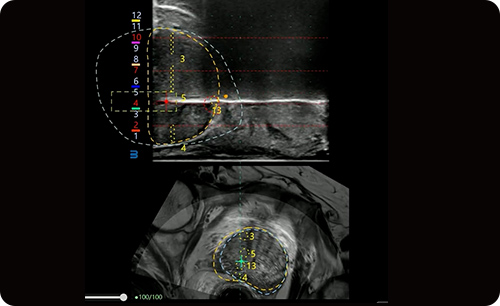

Real-time guide and MRI-Ultrasound fusion in pixel level to achieve precise access.

3D MRI to show the organs and lesions in realtime.